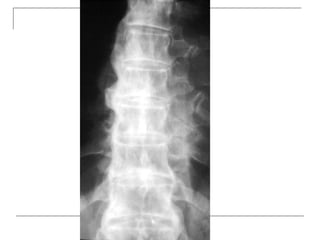

Plain radiograph

   AP

-loss of lumbar lordosis

-reduced disc space

-osteophytes

-deformity

-fracture (increase interpedicular distance)

-osteoporosis

-pedicle disruption

   Lateral

-fracture/wedging

-kyphosis

-spondylolisthesis

   Oblique

-spondylolysis (SCOTTIE DOG)

Plain x-rays

Plain radiograph  AP -loss of lumbar lordosis -reduced disc space -osteophytes -deformity -fracture (increase interpedicular distance) -osteoporosis -pedicle disruption

Lateral -fracture/wedging -kyphosis -spondylolisthesis  Oblique -spondylolysis (SCOTTIE DOG)